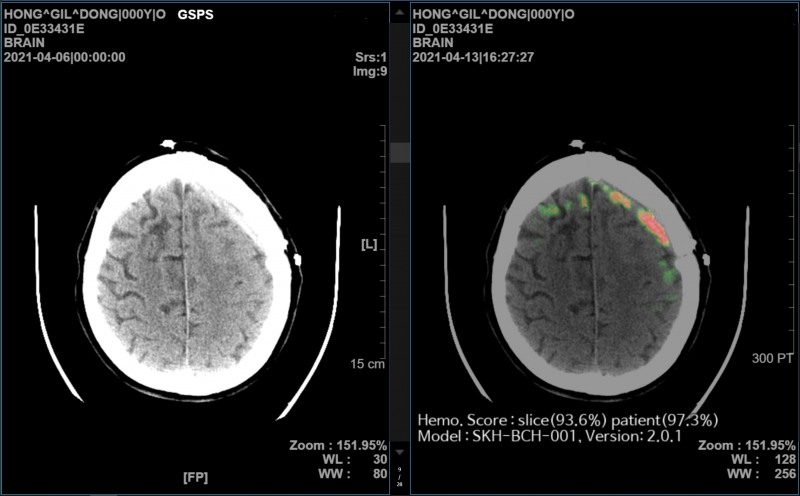

SK㈜ C&C가 개발한 AI 뇌출혈 영상 의료 솔루션 ‘메디컬 인사이트 플러스 뇌출혈(Medical Insight+ Brain Hemorrhage)’의 효과성을 입증한 논문이 네이처 파트너 저널인 ‘디지털 메디신’에 게재됐다. 사진 제공=SK C&C

‘메디컬 인사이트 플러스 뇌출혈’은 뇌 CT 영상을 수초 내로 분석해 출혈 위치와 이상 여부를 의료진에게 바로 알려주는 AI 뇌출혈 진단 보조 솔루션이다.

이번 연구에서 비영상의학전문의들이 AI 뇌출혈 진단 보조 솔루션의 도움을 받으면 영상의학전문의 수준의 진단 결과 정확도를 얻을 수 있다는 점이 입증됐다.

의료진을 전공별로 ▲비영상의학전문의 ▲영상의학전문의 ▲신경두경부 영상의학전문의 그룹으로 나누어 AI가 뇌출혈 진단에 미치는 영향을 분석한 결과, 모든 그룹에서 AI의 도움을 받았을 때 진단 정확도의 향상을 보였다. 특히 비영상의학전문의의 경우 가장 큰 도움을 받을 수 있는 것으로 나타났다.

‘메디컬 인사이트 플러스 뇌출혈’이 의료 기관별로 사용하는 다양한 CT장비 영상을 높은 수준의 정확도로 일관되게 분석한다는 점 또한 확인됐다.

한국지능정보화사회진흥원에서 구축한 약 5만명의 환자 데이터를 대상으로 ‘메디컬 인사이트 플러스 뇌출혈’의 AI 자체 진단 성능을 검증했을 때, GE, 필립스(Philips), 지멘스(Siemens), 도시바(Toshiba) CT 장비 모두에서 98~99%의 높은 진단 정확도를 보여줬다.